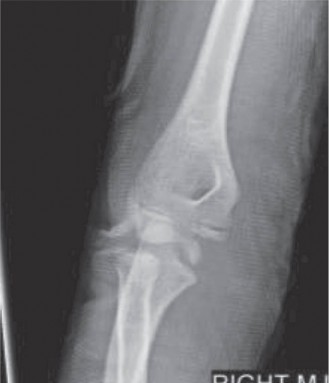

CASE 10 You are called to the emergency room to evaluate a 13-year-old male com…

CASE 8 A 7-year-old girl is transferred to the ER after suffering an injury pl…